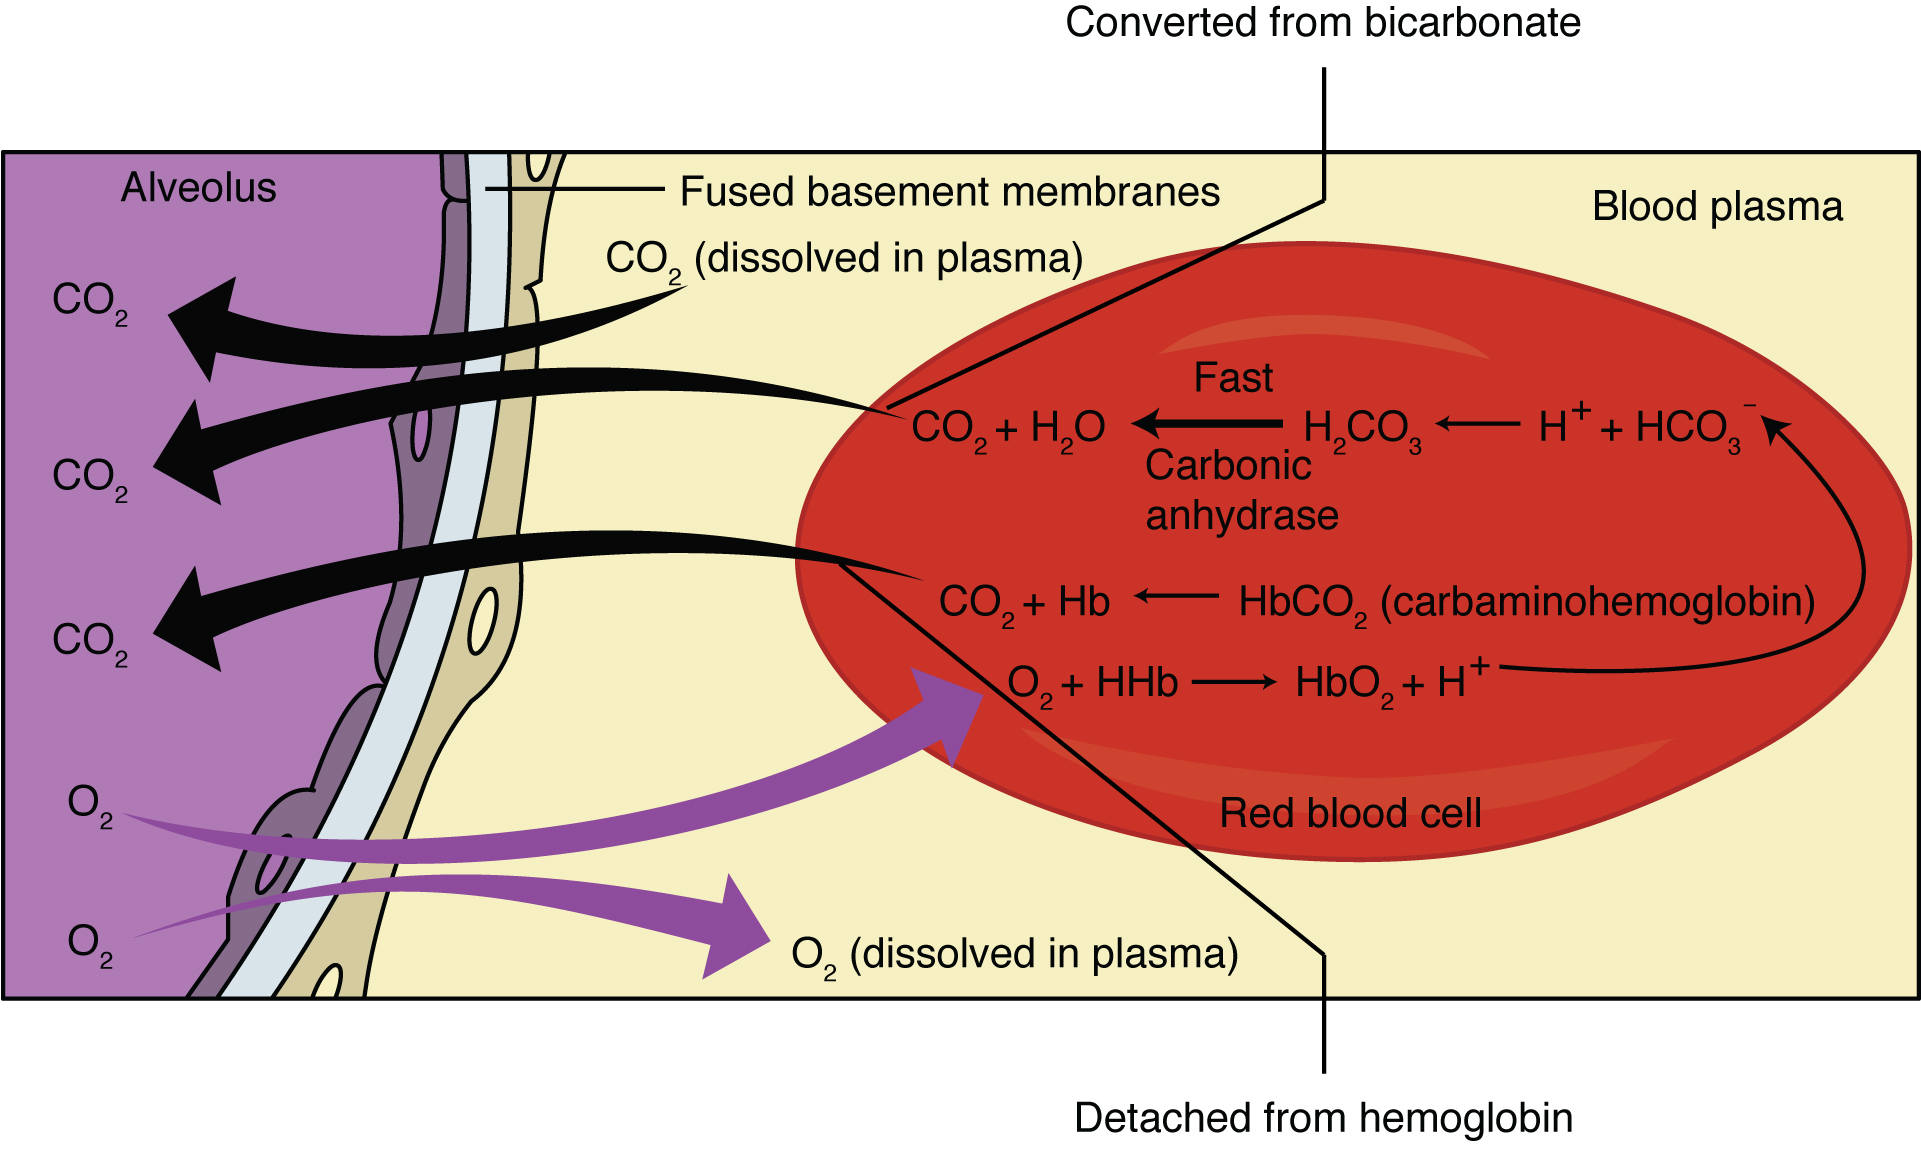

Hypercapnea – is also known as hypercarbia. It is a condition related to high carbon dioxide levels in the body. Carbon-dioxide can get built up in the blood if the body doesn’t successfully get rid of it within time. Conditions that either increase the levels of carbon-dioxide in the body or prevent the waste carbon-dioxide from getting to the lungs and discarded are usually the main causes of hypercapnea. Illnesses related to lung, brain, muscles and nerves are usually the most common causes. Hypercapnia is different to hypoxemia as hypercapnia is the condition with high carbon-dioxide levels in blood whereas hypoxemia is low oxygen levels in blood.